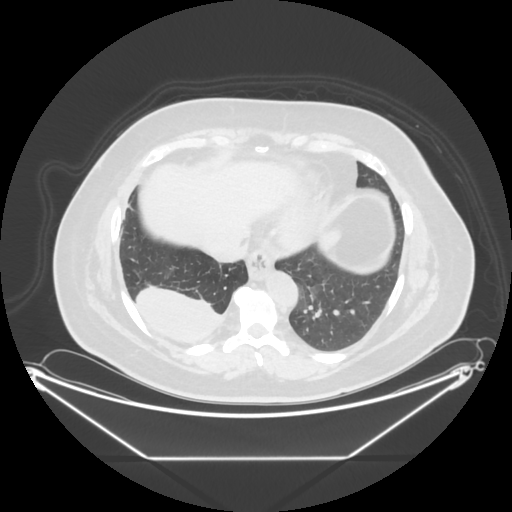

Original VENOUS CT scan

Full window (WL 1023.5, WW 4095 β†’ Low βˆ’1024, High +3071)

Lung window (WL -600, WW 1500 β†’ Low βˆ’1350, High +150)

Mediastinum window (WL 40, WW 400 β†’ Low βˆ’160, High +240)